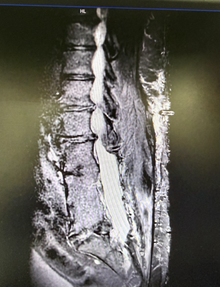

from clipboard

电极植入到位